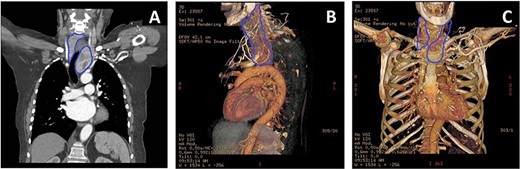

An 83-year-old female with symptomatic (New York Heart Association Functional Classification III symptoms) critical aortic stenosis (AS), (peak gradient 105 mmHg) was admitted for elective AVR via mini-sternotomy after being found unsuitable for transcather aortic valve implantation. At pre-admission, the patient was incidentally found to have subclinical palpable thyroid goitre with tracheal deviation (Fig. 1A). A subsequent computed tomography (CT) scan showed an 8-cm paratracheal thyroid hemi-goitre, extending retrosternally and abutting the ascending aorta and arch (Figs 1B and2).

(A) CT thorax showing the extension of the retrosternal goitre (blue outline), causing tracheal deviation with extension and abutting the distal ascending aorta and arch. (B) 3D-reconstructed CT thorax lateral view highlighting goitre (blue outline) relationship with respect to ascending aorta and arch, and other mediastinal structures. (C) 3D-reconstructed CT thorax allowed planning of mini-sternotomy in relation to goitre position.

The goitre’s position would invariably make aortic cannulation and cross-clamping to perform the AVR difficult. It was deemed that the goitre needed removal first. However, the retrosternal position meant that normal cervical excision would be challenging and risky. Furthermore, due to the severe nature of the AS, she was considered unsafe to undergo thyroidectomy as a primary procedure. Endocrine surgeons were consulted and consensus dictated that combined procedure would be the best approach utilizing a mini-J sternotomy to aid in excision of the hemi-goitre prior to completing the AVR. 3D imaging was reconstructed to determine the anatomical relations in detail and plan the combined surgical approach meticulously (Fig. 2B and C).